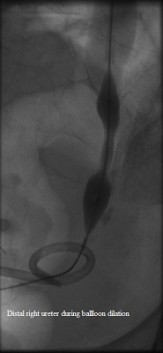

Distal right ureter during dilation

Published July 12, 2014 at 163 × 353 in Bilateral insertion of nephroureteral stents after balloon dilation of malignant obstruction of the distal ureters. Ken U. Ekechukwu, MD, MPH, FACP..